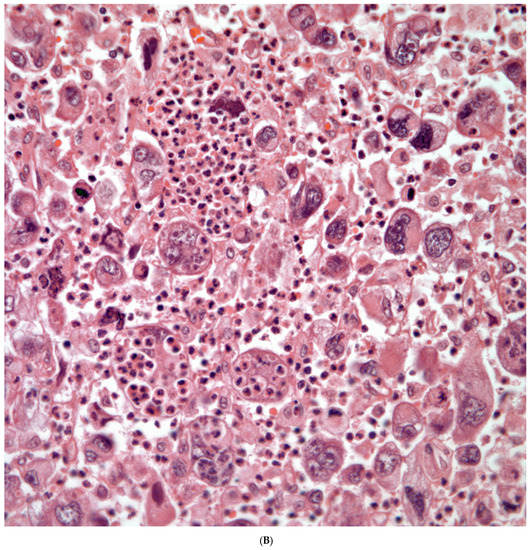

Giant Cell Carcinomas: These tumors may show predominantly a neoplastic cellular proliferation composed exclusively of multinucleated giant cells or a predominantly giant cell carcinoma (Figure 5A,B) or associated with a conventional non-small cell carcinoma like adenocarcinoma or squamous cell carcinoma. The giant cell carcinoma may show giant cells of the syncytiotrophoblastic, osteoclastic, or null cell type. The giant cell carcinomas of the null cell type characteristically show a prominent inflammatory background and giant cells engulfing inflammatory cells (emperipolesis) (Figure 6A,B). The tumors composed of osteoclast-like giant cells show giant cells like those described in bone tumors (Figure 7A,B).

Figure 5.

(A) Predominantly giant cell carcinoma; (B) Marked atypia and numerous multinucleated malignant giant cells.